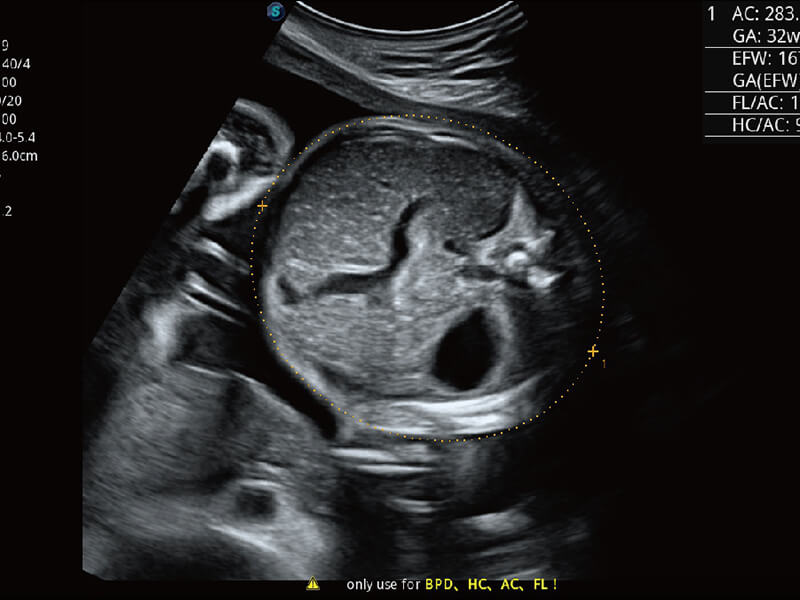

S60探头工艺,从前端信号处理每一个环节采集无损声学数据,真实还原组织原貌,再现解剖细节。

S-Fetus 产科扫查助手

• 缩短

操作时间

• 提升

准确率

• 单次

按键操作